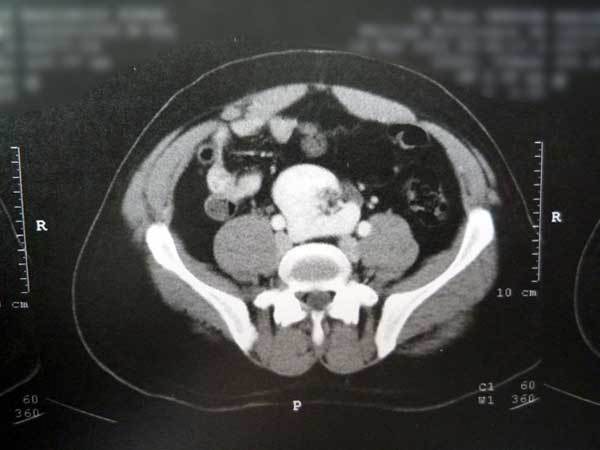

Quel est votre diagnostic ? Un rein ectopique Il s'agit bien d'un rein ectopique. Un anévrisme de l'aorte abdominale Un hémangioblastome Une maladie de Castleman Un léiomyosarcome Un abcès rénal OK Valider mes réponses